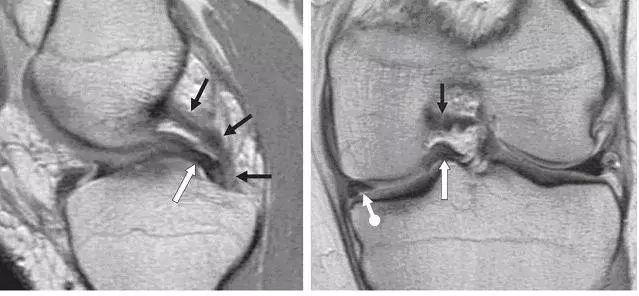

左图:外侧半月板,由于横截面面积一致,故在MRI 上可见外侧半月板前后角(纵向白色箭头)形状和大小较相似。上下腘肌半月板纤维束(黑色箭头)在外侧半月板后角处,形成裂孔,中间有腘肌腱(水平白色箭头)通过。右图:内侧半月板,可见后角(白色圆箭头),略大于前角(白色直箭头)

内外侧半月板的前角通过半月板横韧带相连,该横韧带与半月板中间的空间有其他组织(如关节液等),呈现高信号,在磁共振上容易误诊为半月板撕裂。

前后半月板股骨韧带(Humphry 和 Wrisberg 韧带 )分别位于后交叉韧带的前后。连接外侧半月板后角和股骨内侧髁外面。

左图:横断面 T1 像显示半月板横韧带连接内侧半月板(白色圆箭头)和外侧半月板(白色直箭头)的前角;右图:经过半月板横韧带(黑色箭头)的矢状面,可见半月板横韧带与半月板前角之间的间隙呈现高信号(白色箭头),易误诊为半月板撕裂。

左图:经过后交叉韧带的矢状面,显示连续均质低信号的后交叉韧带(黑色箭头),其前方是半月板股骨前韧带(Humphry 韧带,白色箭头)。右图:冠状位片显示半月板股骨后韧带(Wrisberg 韧带,黑色短箭头不带圆点)从外侧半月板后角(黑色长直箭头)连接到股骨内侧髁外面。同时可见腘腓韧带(白色箭头)从腓骨头到腘肌腱(黑色短圆箭头),P 为后交叉韧带。